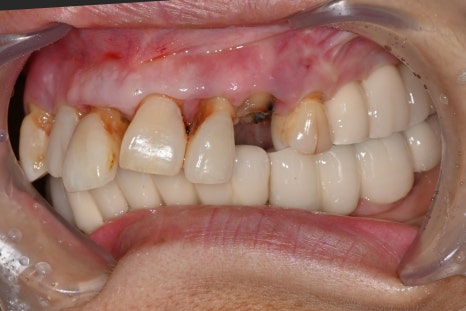

어금니와의 교합까지 고려한 치료

앞니 임플란트는 앞니만 맞춘다고 끝나는 치료가 아닙니다.

어금니 교합까지 함께 맞춰야

전체적인 균형이 유지됩니다.

이번 케이스에서도

어금니 교합 유지

전방유도 조정

전체 교합 균형 개선

이 함께 진행되었습니다.

임플란트치과에서는

이러한 전체적인 설계가 중요합니다.

치료 후 변화

치료 후 환자분은을 경험하셨습니다. 특히

“내 치아처럼 자연스럽다”는 반응을 보이셨습니다.

자연스러운 앞니 회복

미소 개선

발음 안정

식사 기능 회복